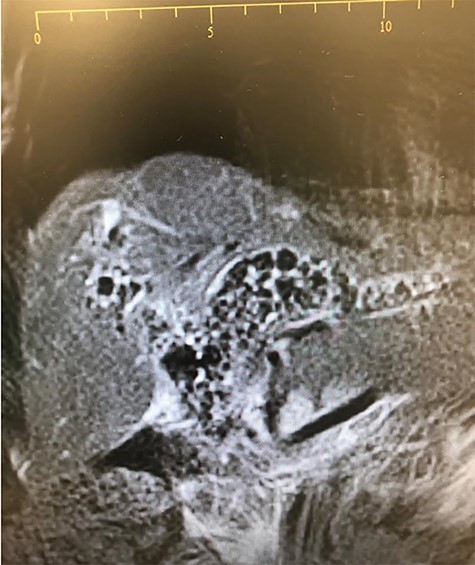

We present a 79-years-old female patient who presented on the 31 January 2019 with worsening recurrent right upper quadrant pain, dark urine, chills and tiredness for 12 months. She was a known diabetic and hypertensive controlled on medications. Her past surgical history was notable for having had an open cholecystectomy for symptomatic cholelithiasis in 2016. The same year post cholecystectomy, she was found to have retained common bile duct (CBD) stones. She had endoscopic retrograde cholangiopancreatography (ERCP), during which a complete clearance of the stone was not achieved and she was stented with a completely covered metal stent. There was no follow-up until she got symptomatic in 2019 and she presented with cholangitis. Her blood workup showed an obstructive picture. The abdominal ultrasound was not diagnostic. She was started on analgesia and antibiotics. A differential diagnosis of a blocked stent was made. She had an ERCP on the 04 February 2019. An old stent was found, which could not come out. An extraction balloon was used to clean the old stent of debris and small stones and a 10 Fr × 9 cm plastic stent was deployed. On table, cholangiogram showed dilated ducts with multiple stones in the CBD extending into the left and right hepatic ducts and the first order ducts bilaterally (Fig. 1). MRCP confirmed the cholangiogram findings (Fig. 2). On 18 February 2019, she had open bile duct exploration and Roux-en-Y hepaticojejunostomy reconstruction (wide anastomosis). The stents and multiple stones were removed (Fig. 3). She had an uneventful post-operative course. At her first follow-up, 6 weeks later, she had normal liver function tests and felt much better.

Our case had a rather rare finding with stones extending from the CBD, into the right and left hepatic bile duct and the first-order intrahepatic biliary ducts on both sides. Most of the reported cases had only CBD stones [1, 4, 5]. This was the first case with such an extensive biliary tree involvement with stones. The real cause of the burden of stones in the biliary tract is unknown. It is noted, however, that our case was the only one reported with a forgotten metal stent while the other case reports had plastic stents [1, 4, 5]. Whether this is contributory to the burden and extent of stones involvement is unknown.